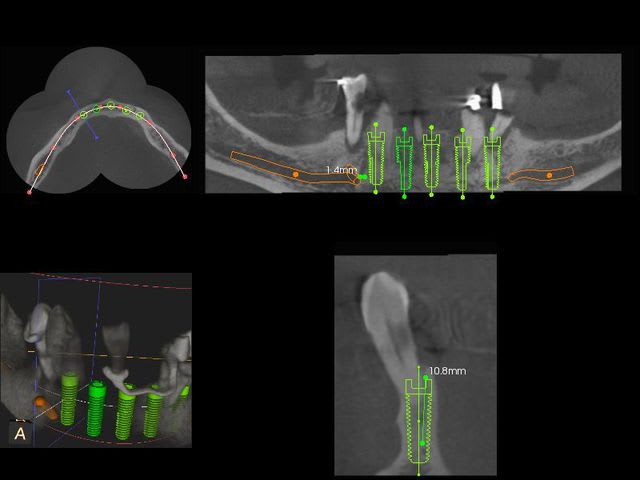

Ce matin j'ai fait la pose de 5 implants symphysaires en extraction implantation immédiate.

Je trouve que les implants sont tous quasiment sur une même ligne car l'arcade n'est pas assez courbe dans le secteur antérieur.

Le problème est que l'émergence des mentonniers se fait en dessous des 4.

Comment gérez vous cela en terme d'extension distale du pilotis ?

Le vrai problème vient du fait qu'il a ses foramina au dessus des 4 et pas des 5 comme on le retrouve habituellement.

Excusez le hors sujet, mais j'ai une question de béotien, Dudule sur ta coupe transversale on a l'impression que tu n'as aucune marge entre le diamètre de ton implant et les corticales, comment se fait-ce ? As-tu choisi au final des implants plus étroits ?